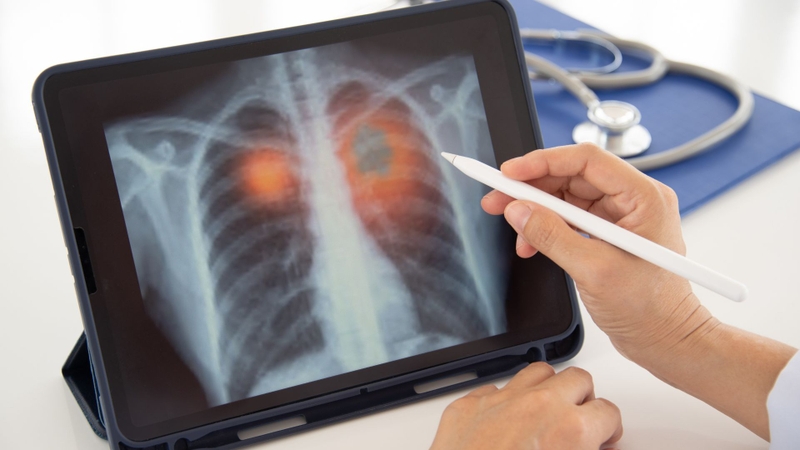

Chụp X quang viêm phổi do phế cầu là phương pháp chẩn đoán hình ảnh giúp bác sĩ phát hiện tổn thương phổi, xác định mức độ viêm và theo dõi tiến triển bệnh. Đây là bước quan trọng khi người bệnh có triệu chứng sốt cao, ho, đau ngực hoặc khó thở.

Chụp X quang bệnh viêm phổi do phế cầu là kỹ thuật sử dụng tia X để ghi lại hình ảnh phổi, giúp phát hiện các vùng phổi bị viêm, đặc biệt là hình ảnh đông đặc thùy phổi - dấu hiệu thường gặp trong viêm phổi do vi khuẩn phế cầu.

Chụp X quang giúp:

Việc phân biệt này rất quan trọng vì hướng điều trị sẽ khác nhau. Tuy nhiên, X quang chỉ là một phần trong chẩn đoán. Bác sĩ còn dựa vào triệu chứng lâm sàng, xét nghiệm máu và đôi khi xét nghiệm đờm để xác định chính xác nguyên nhân.